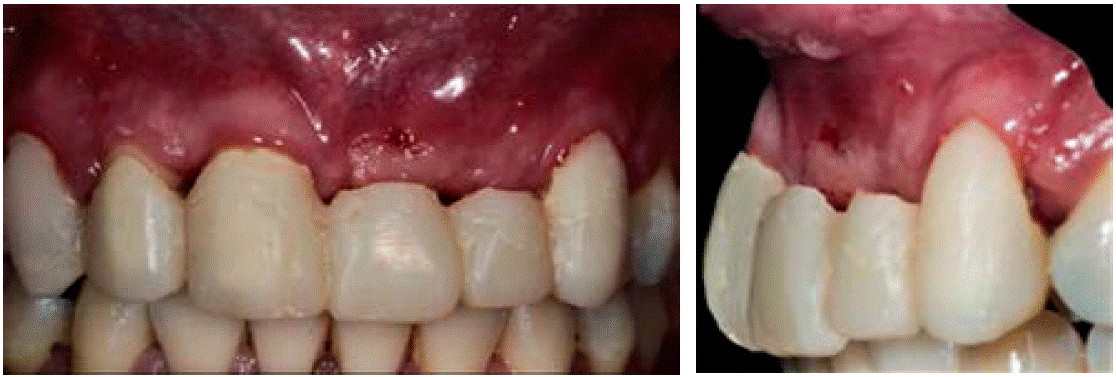

La paciente acudió a consulta un mes después de la intervención quirúrgica. A la exploración intraoral se observaron tejidos blandos afrontados sin presencia de infección ni exposición de la lámina ósea y se retiraron puntos de sutura. La paciente no refirió molestias (Figuras 10AyB).